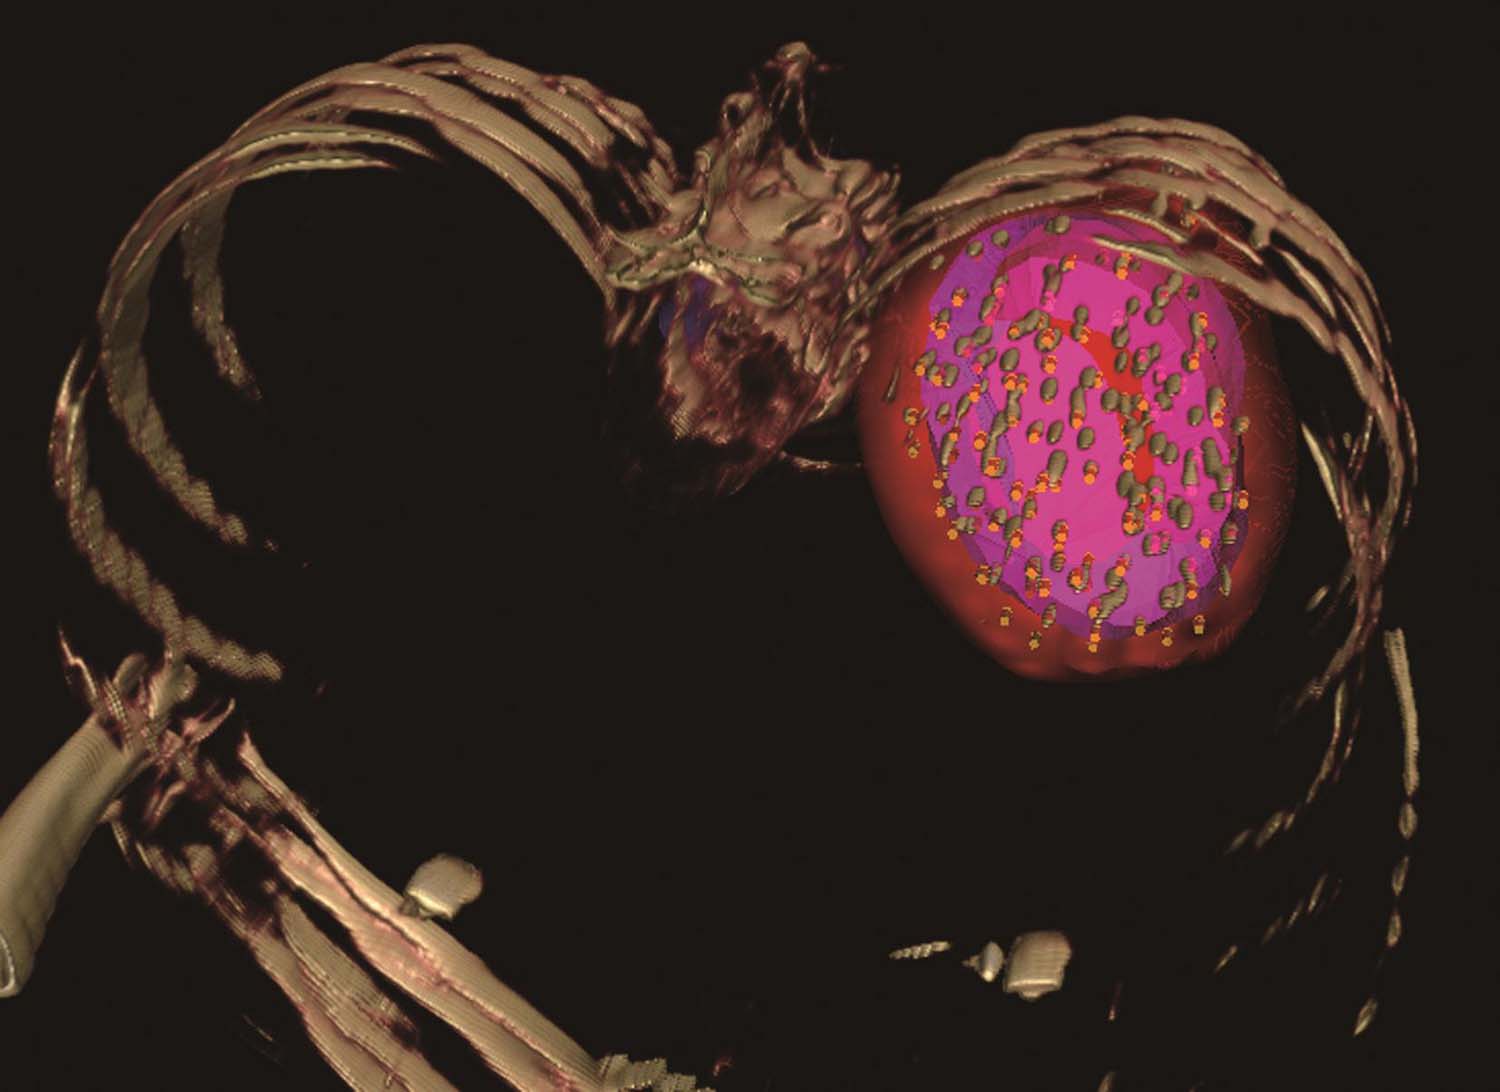

图4-3-2 术前布针三维重建图

图4-3-3 模板引导,完成选择层面的进针

图4-3-4 依次完成其他层面的进针

图4-3-5 完成肺门病灶的进针

图4-3-6 完成肺门病灶的粒子植入

图4-3-7 术后等剂量分布图

例1 患者男性,72岁,左肺鳞癌侵犯胸壁并同侧肺门淋巴结转移,T4N1M0。2018年1月16日行共面模板引导放射性粒子植入术(图4-3-2~图4-3-7)。